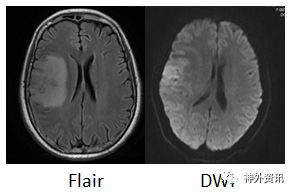

患者10天前无明显诱因出现自觉左侧头面部及肢体发热,伴左上肢肢体乏力及口齿不清,至我院就诊。头部增强MRI示:右侧额叶占位性病变,T1低信号,T2高信号,强化后呈不均匀强化(图1)。以“颅内占位性病变”收住入院。

图1.头部MRI增强右侧额叶可见一片状不规则肿块; T1WI上为稍低信号,T2WI上为略高但混杂信号,有不均匀明显强化,约2.8cm×4.3cm×1.9cm。伴有周围水肿。有轻度占位效应。灌注成像:强化肿块区CBF、CBV增高。磁共振波谱:额病灶及周围NAA峰下降,Cho峰升高,伴有脂质乳酸峰出现,提示肿瘤性病变。